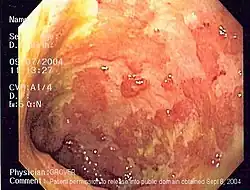

La coloscopie montre typiquement un aspect inflammatoire du côlon, naissant au niveau du rectum et remontant plus ou moins haut de manière continue. Cette continuité des lésions est parfois inconstante[3]. La sévérité de la maladie dépend en partie de son extension.